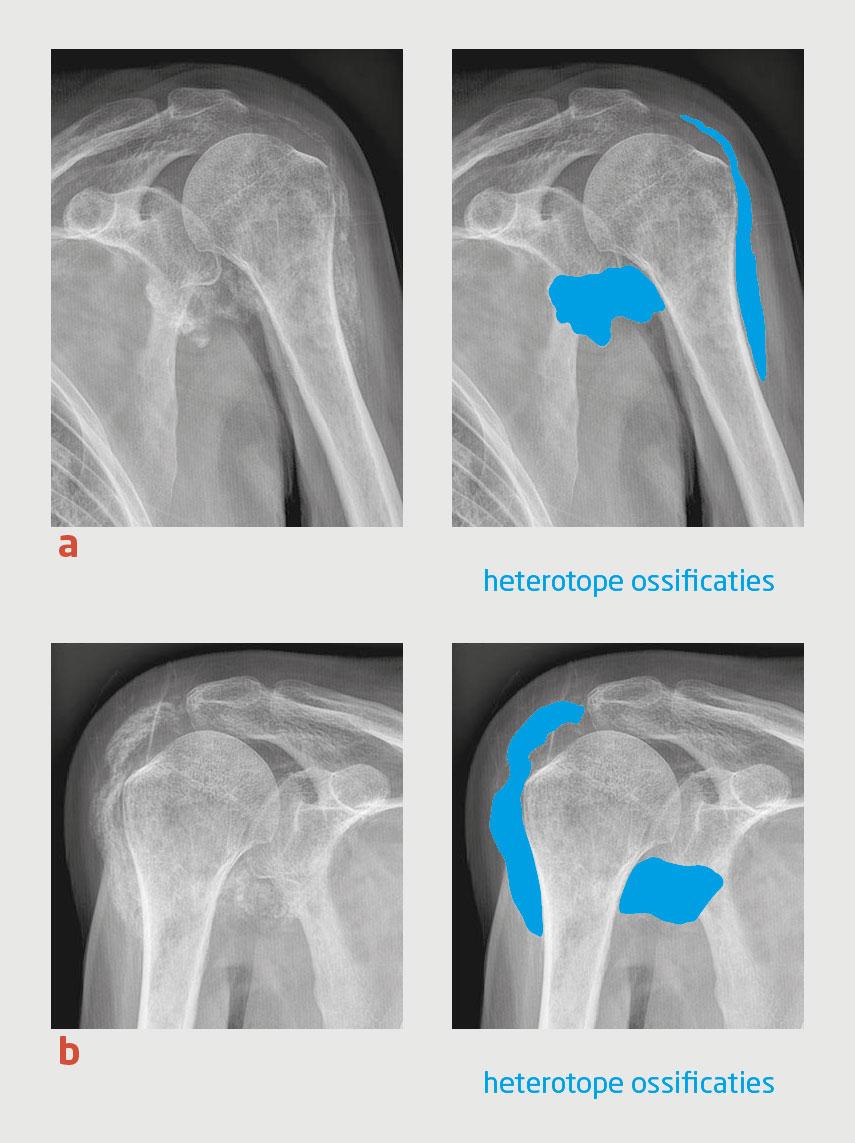

Figuur 1 | Heterotope ossificaties rondom beide glenohumerale gewrichten van patiënt A.

Röntgenfoto’s van (a) de linker en (b) de rechter schouder van patiënt A. Uitgebreide heterotope ossificaties zijn zichtbaar in de weke delen rondom de beide glenohumerale gewrichten.